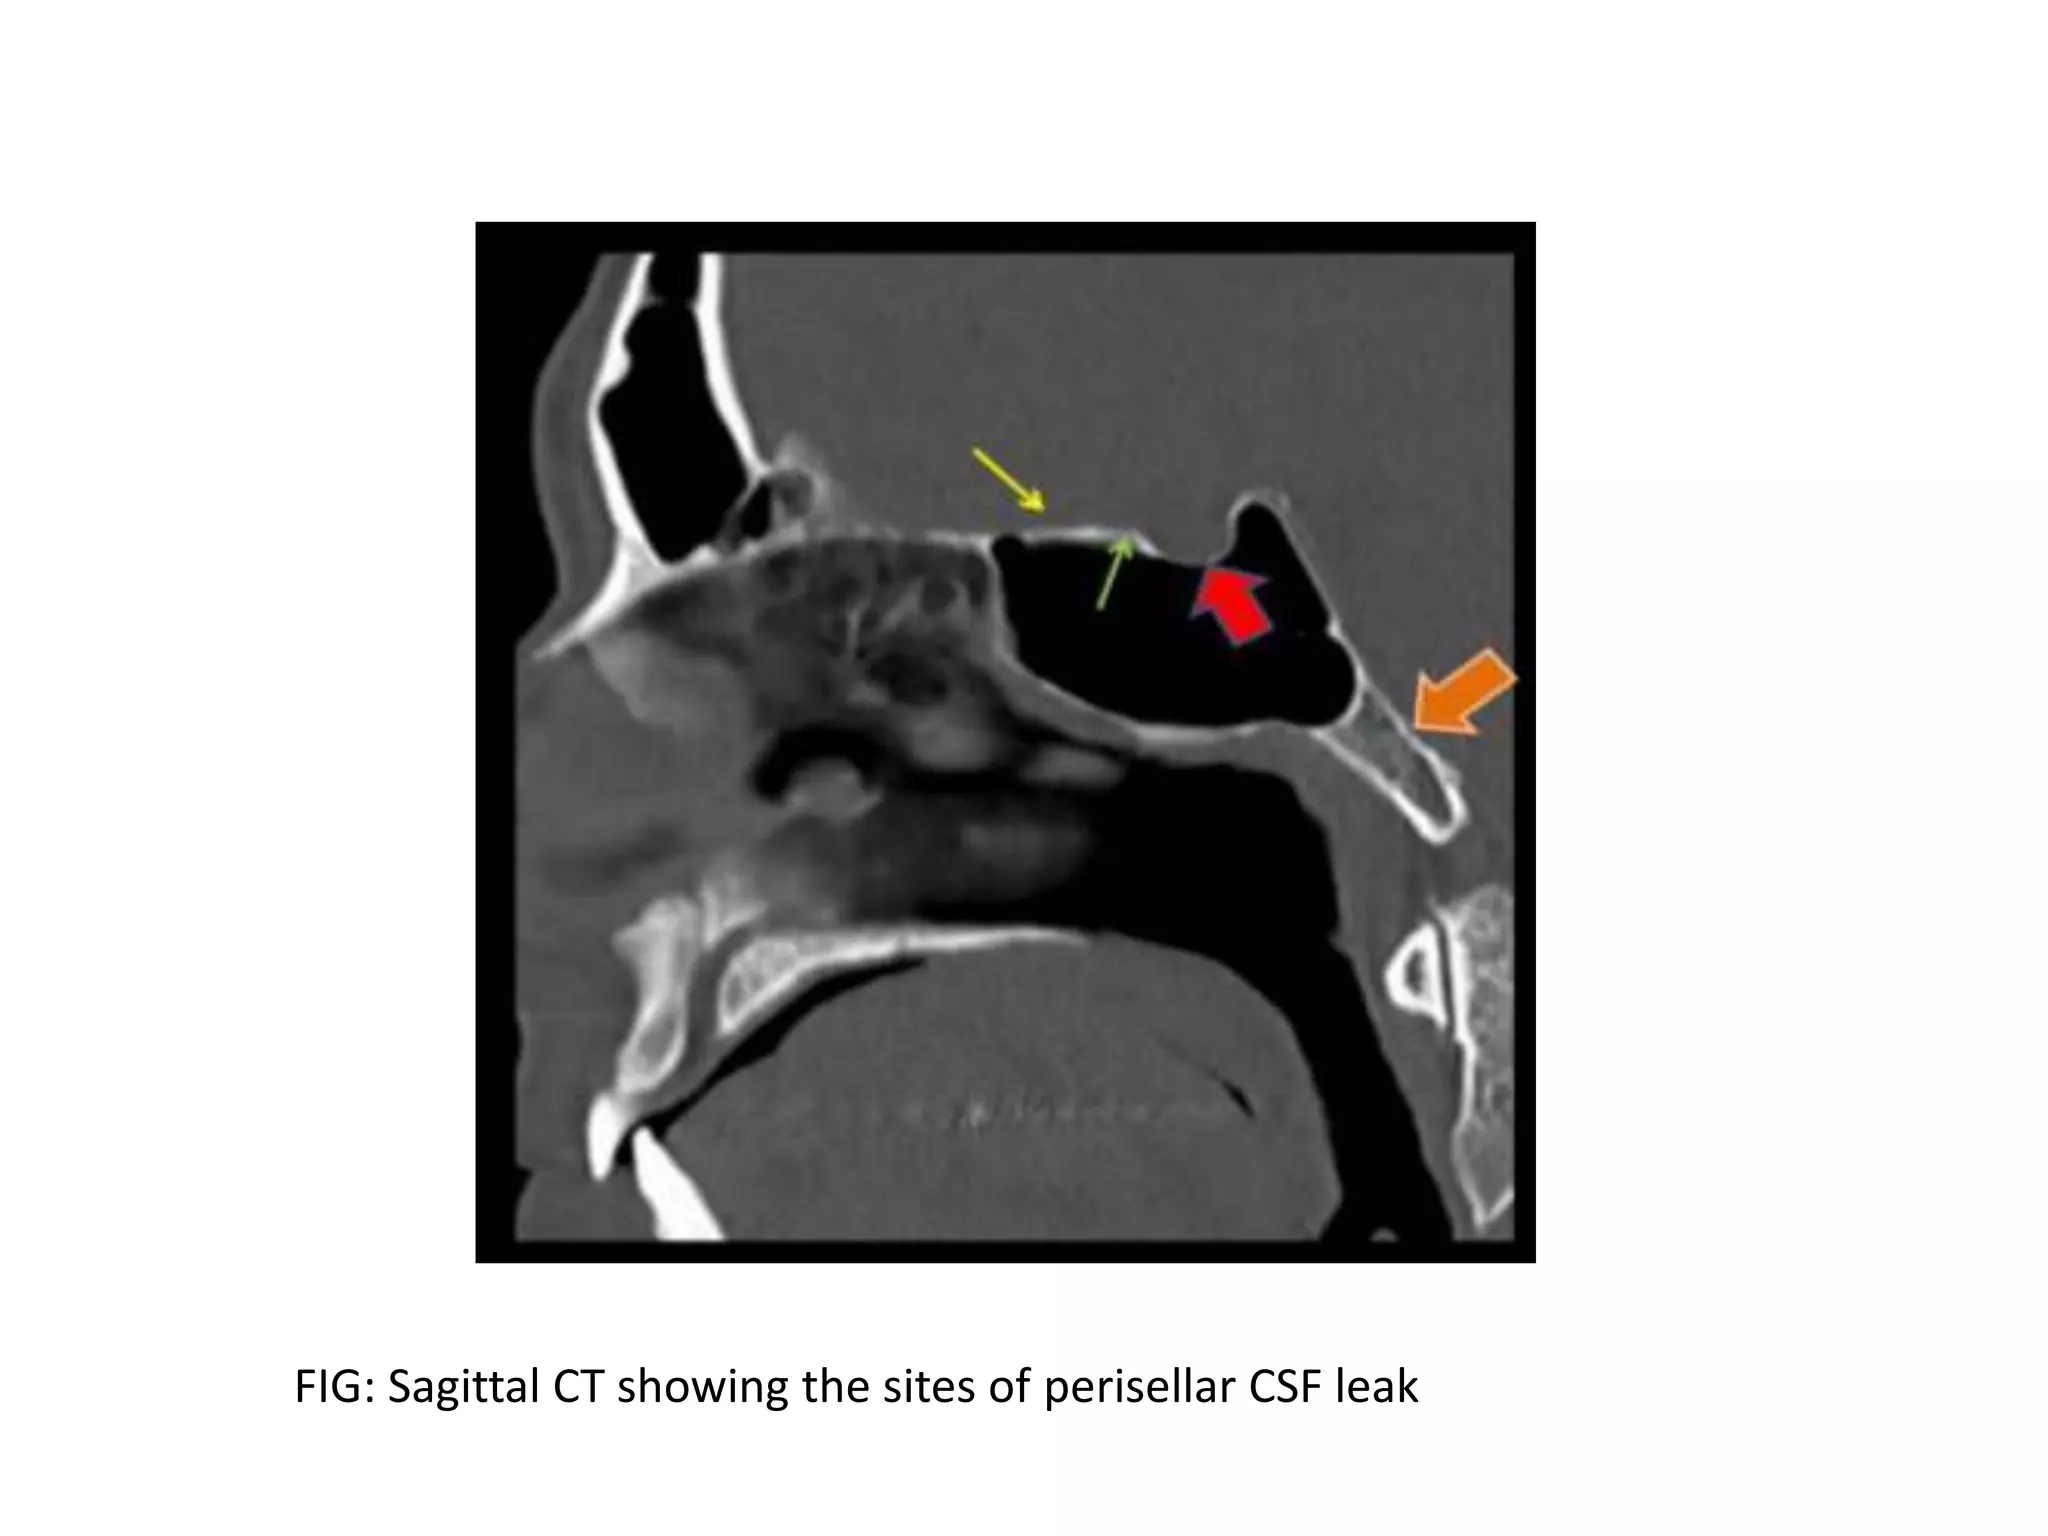

FIG: Sagittal CT showing the sites of perisellar CSF leak

FIG: Sagittal CTshowing the sites of perisellar CSF leak

• #24  Spontaneous CSF fistulas may occur anywhere in the skull base, but they are more common at the cribriform plate, tegmen tympani or sphenoid sinus. Redline :lamella lateralis(a thin vertical strut joining the medial aspect of ethmoidal roof with cribriform plate.)

• #25  Thin green :tuberculum sellae Thick red arrow:sellar floor Thick orange:spheno-occipital synchondrosis